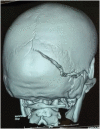

Supratentorial-infratentorial epidural hematomas (SIEH) are a rare occurrence following traumatic head injuries, representing only 2% of traumatic epidural hematomas. Given the unique anatomical characteristics of the infratentorial region, mainly its small size, surgical intervention is commonly undertaken to alleviate the pressure on the posterior fossa components. Consequently, there is ongoing debate surrounding the optimal surgical approaches.In this report, we present four cases of SIEH that were treated surgically. Furthermore, we conduct a comprehensive review of existing literature, encompassing clinical, radiological, and therapeutic aspects associated with this condition.SIEH are uncommon post-traumatic lesions that require urgent and individualized management on a case-by-case basis, as guided by multiplanar cerebral computed tomography scan findings. Preoperative planning is essential; however, intraoperative exploration and identification of transverse sinus and torcula lesions are crucial for optimal patient care. The surgical approach may be modified intraoperatively based on the nature and extent of these lesions. In all cases, prompt hematoma evacuation and meticulous hemostasis are the two primary objectives of this surgery.